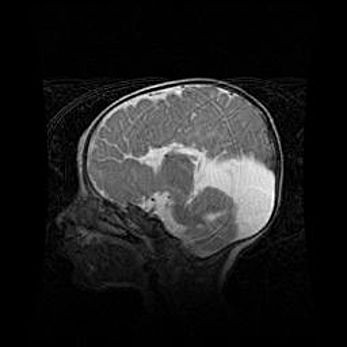

Аномалия Денди-Уокера. Признаки гипоплазии мозолистого тела.

Возраст: 5 месяцев 3 дня

Вес: 5550 г

Пол: мужской

Окружность головы: 39 см

Срок гестации: 40 недель

Аномалия Денди-Уокера – это порок развития головного мозга, для которого характерна триада симптомов: гипотрофия или аплазия червя мозжечка и/или полушарий мозжечка, расширение четвёртого желудочка с формированием ликворной кисты задней черепной ямки, гипертензионная гидроцефалия различной степени.

Гипоплазия мозолистого тела относится к дефектам внутриутробного этапа развития мозговой ткани, возникающим в процессе закладки структур головного мозга, что происходит на начальных этапах развития эмбриона.